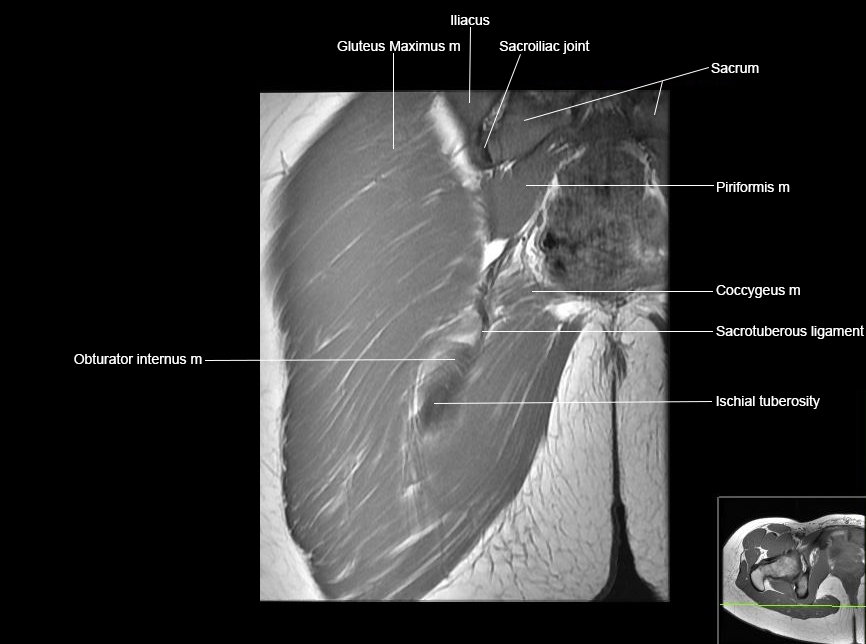

MRI Hip Anatomy

Scroll using the mouse wheel or the arrows